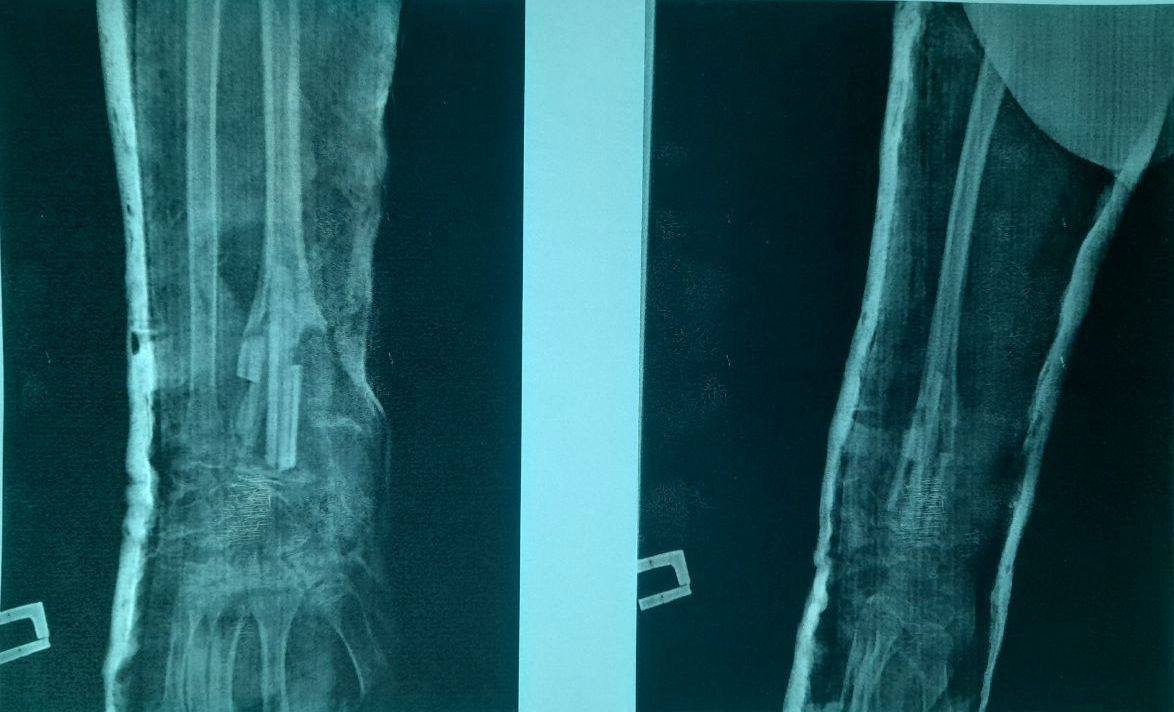

В Оренбургской областной детской клинической больнице провели серьезное хирургическое лечение 12-летнему ребенку со сложным диагнозом. У подростка выявили доброкачественное опухолеподобное поражение костей, состоящее из многочисленных сосудистых пространств с кровью.

У юного пациента диагностировали аневризмальную кисту лучевой кости, сообщили в клинике. Мальчика уже оперировали в ноябре 2022   года. Ему проводили экскохлеацию образования и гистологическое исследование. Затем сделали костную пластику аллотранспантатом. Тогда на гистологии и подтвердился диагноз «аневризмальная киста».

Специалисты промыли полость кисты аминокапроновой кислотой. Однако через полгода патология не изменилась в лучшую сторону. Повторную операцию назначили на 23 сентября. Хирурги провели ребёнку   резекцию тканей, имеющих патологию. Также врачи провели костную пластику аутотрансплантатом — это собственная костная ткань человека. Сейчас школьник находится под наблюдением врачей областной детской больницы.